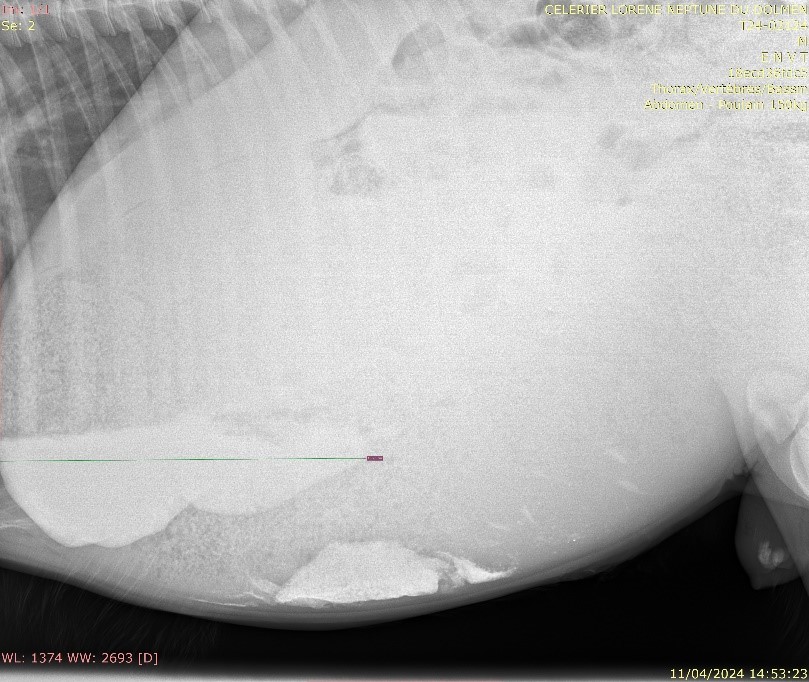

Une radiographie abdominale a révélé une accumulation significative de sable dans le côlon.